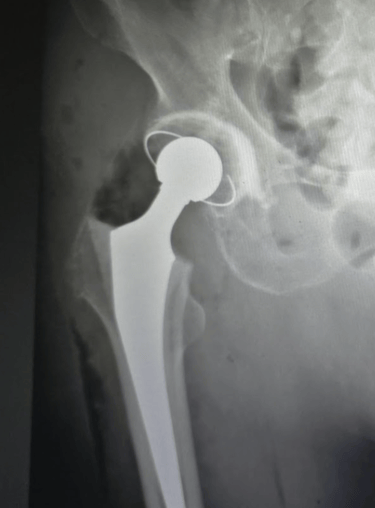

Una prótesis de cadera es un implante que reemplaza la articulación dañada entre el fémur y la pelvis. Está diseñada para imitar la forma y el movimiento de una cadera sana, permitiendo al paciente mejorar su movilidad y el dolor que antes limitaba su vida diaria.

Prótesis total de cadera: Reemplazo completo del acetábulo (cavidad en la pelvis) y de la cabeza femoral.

Hemiartroplastía: Se sustituye solo la cabeza femoral, habitualmente en fracturas específicas en pacientes mayores.